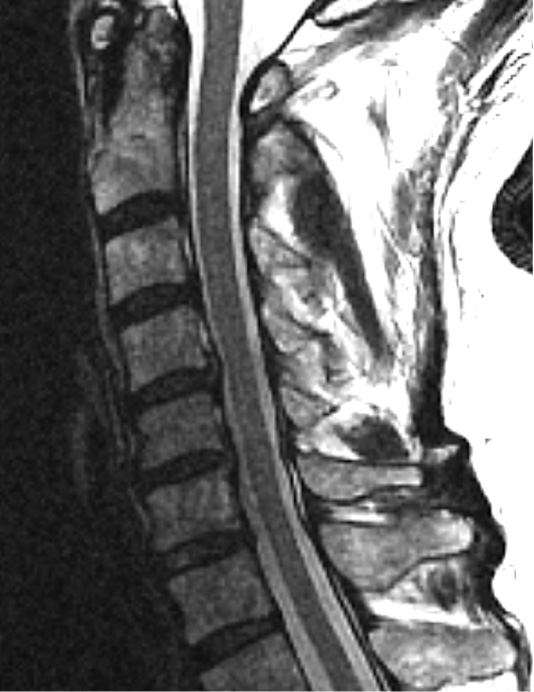

MRIs illustrated mild degenerative disc disease from C4-6 with disc herniations at both C4-5 and C5-6. The axial slice through C4-5 showed a right central disc herniation causing central and mainly right-sided foraminal stenosis. The axial slice through C5-6 showed a central disc herniation also causing central and mainly right-sided foraminal stenosis. The axial slice through C6-7 showed a left-sided disc herniation causing some left-sided foraminal stenosis, however, the patient did not demonstrate any left-sided symptoms.

Upon examination, the patient had good motion on flexion-extension, so fusion was not considered at all. My operative plan was to use prodisc cervical devices and replace both discs at C4-5 and C5-6, giving me the flexibility to use either a domed or flat implant.